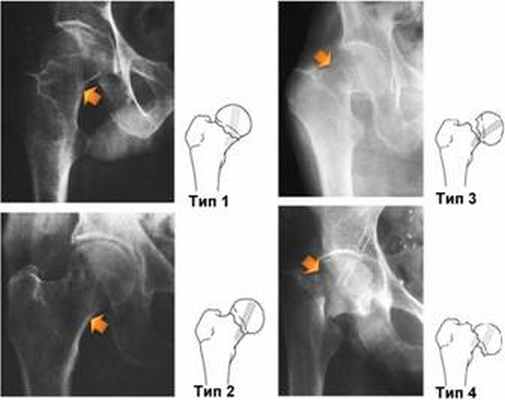

Виды переломов шейки бедра и их классификация

Рентгенограммы различных вариантов переломов и их схематичное изображение на рисунке справа.

Существуют следующие виды переломов, например, перелом шейки бедра со смещением, без смещения, вколоченный, субкапитальный перелом, латеральный, трансцервикальный, чрезвертельный, вертельный, базальный, медиальный перелом шейки бедра и др. Все они различаются по определенным признакам. Рассмотрим основные из них.